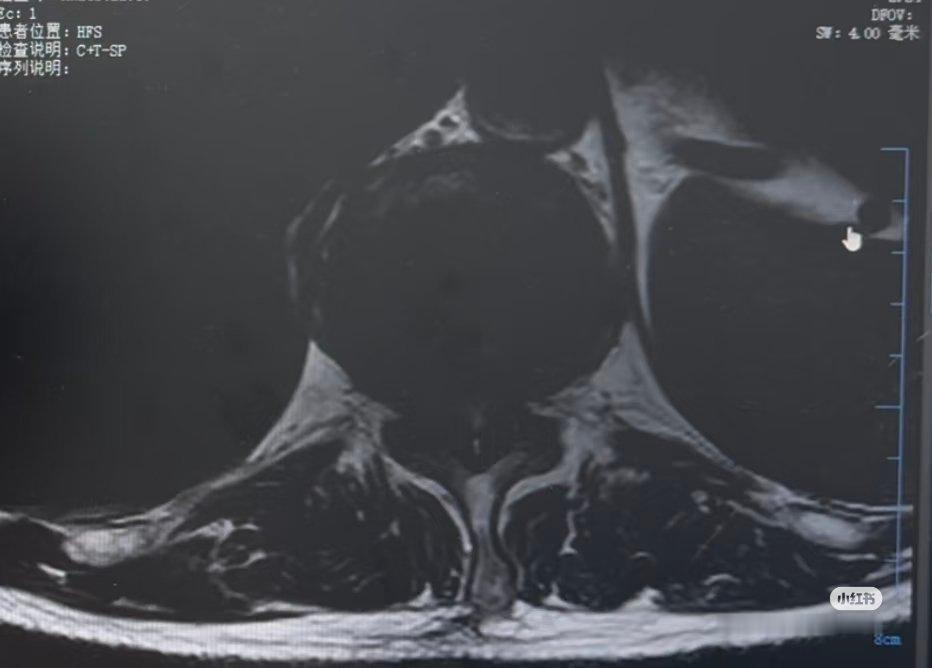

【胸椎微创:腰椎手术最难,颈椎最简单,胸椎最危险】术后第二天,患者下地走路,感觉不错。胸椎手术最危险,很容易瘫痪。我的颈椎微创,胸椎微创的手术量在整个地区可能是最多的了,经验丰富,但是每次做的时候还是如履薄冰,如临大敌。这次手术是在外院的飞刀手术。术中发现钙化的韧带把神经压出了一个凹陷,神经膜硬化跟钙化的韧带黏连,分离起来很困难。叫兽每一步都做到了不骚扰神经,做完自信毫无问题。